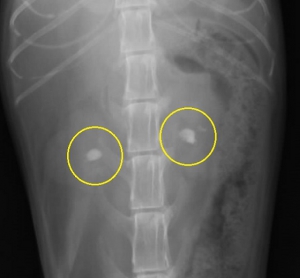

下の写真は両側の腎盂内に比較的大きな腎結石が発見された猫の腹部レントゲン写真です。上写真が縦方向下が横方向のものです。

猫でみられた腎結石のレントゲン写真を左下図に示します。その中で「白く見える3つの影」が腎臓(腎盂内)にある腎結石です。イメージしやすいように結石と腎臓の位置関係を右の模式図に重ねてみました。結石は実際には腎臓の腎盂内にあるので外からは見えません。一番左の結石は尿管に落ちかかっています。